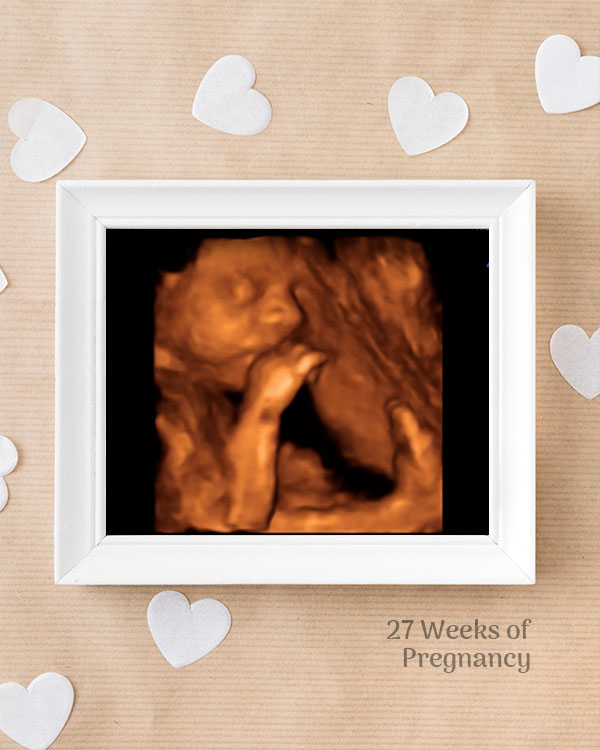

3D / 4D Baby Scan

Mediserv Diagnostics pioneered 4D scanning in the Malabar region. These advanced scans provide realistic images of the baby, allowing detailed evaluation of fetal structures and movements while creating a meaningful bonding experience for parents.